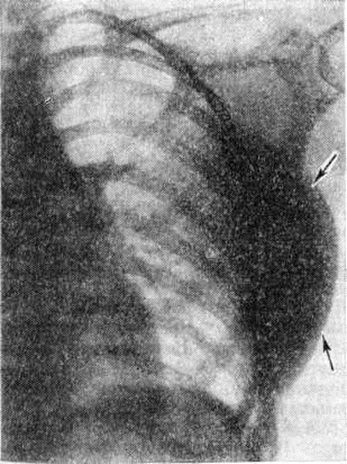

При локализации Липома в грудной клетке, брюшной полости или забрюшинном пространстве рентгенологическое исследование проводится только «жёсткими» лучами с решёткой в условиях искусственного контрастирования газом (пневмомедиастинум, пневморетроперитонеум и другие).

На рентгенограммах Липома представляет гладко-очерченное просветление обычно правильной формы. Просветление, образуемое Липома, как правило, гомогенное, но изредка в нем встречаются мелкие участки обызвествления. Форма просветления зависит от плотности органов, между которыми заключена Липома Подкожная узловатая Липома проявляется в виде чётко очерченного округлой формы образования, интенсивность тени которого одинакова с окружающей жировой тканью (рисунок 2). Большие, длительно существующие Липома вызывают смещение окружающих тканей.

Дифференциальный диагноз при рентгенодиагностике глубоких Липома туловища, шеи или конечностей проводят с натёчным абсцессом, гематомой, кистой, лимфаденитом, гемангиомой, мио или фибросаркомой.